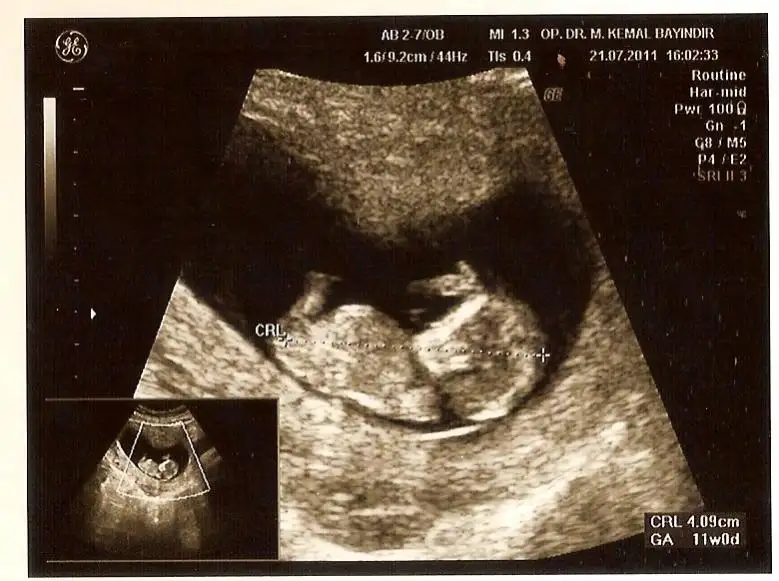

dr soylemeden siz gorun genital nub teorisi ( bebegin cinsiyeti)

himmmm bak burda paralel gibi duruyor nubu

buarada dr un ismi dikkatimi cekti dr bayindir erkek bebek icin bayaa bi yardimci oluyormus yakin olsaydim kesin giderdimm :))

bu oğlumun resmi)geçen sene gitmişdik.Çok güzel 4d boyutlu ultrasonda bakdı ve söyledi.Bu sene de gittim ona,koca bi hastane açmış o.Ama bu sene çok zayıf bi ultrasonda bakdı ve ne fark eder dedi cinsiyet için.20 şubat gelirsin yine bakarız dedi.Ama kız gibi duruyor,ama yanıla bilirim dedi)

kac haftalik canim burda sanki 11 gibi bu haftalar cok yaniltici oluyor baska fotosu varsa koyarmisin